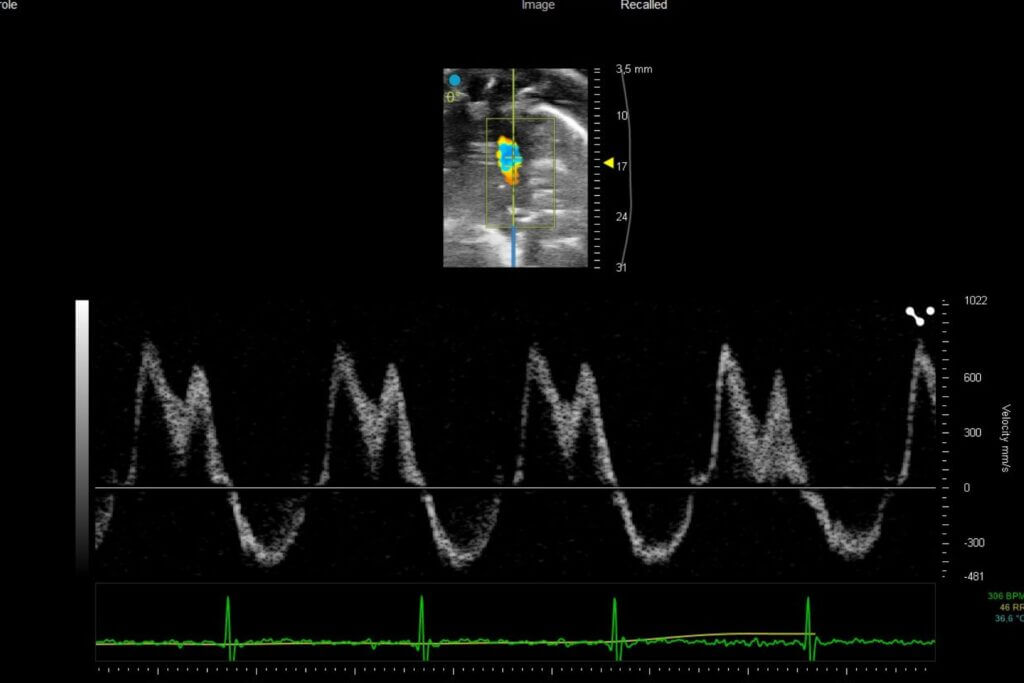

Our platform enables the direct evaluation of therapeutic candidates in both HFrEF and HFpEF models, integrating comprehensive assessments of left ventricular function by echocardiography, cardiac remodeling, and cardio-renal-metabolic interactions.